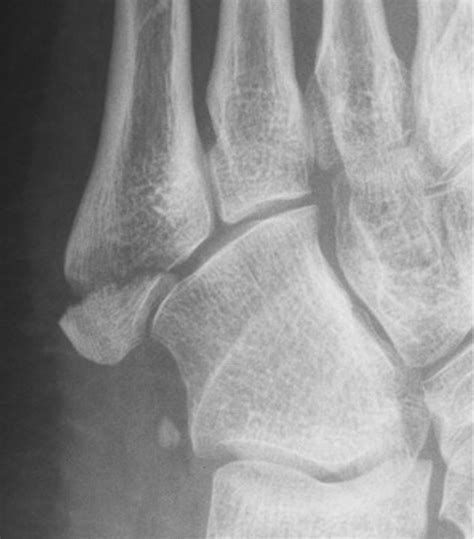

Avulsion fractures are frequently seen in athletes, particularly those involved in sports requiring sudden changes in direction or explosive power. Common sites for these injuries include the ankle, hip, finger, and base of the fifth metatarsal in the foot. When a muscle contracts forcefully, it can pull on its tendon, and if the force is excessive, the bone simply gives way. Because the movement of tendons is constant, the primary goal of medical intervention is complete restriction. Using a cast for avulsion fracture ensures that the tendon does not pull the bone fragment further out of alignment while the healing process begins.

Fifth Metatarsal Short Leg Cast Prevent weight-bearing pressure

Ankle (Malleolar) Fiberglass/Plaster Cast Restrict joint rotation and inversion